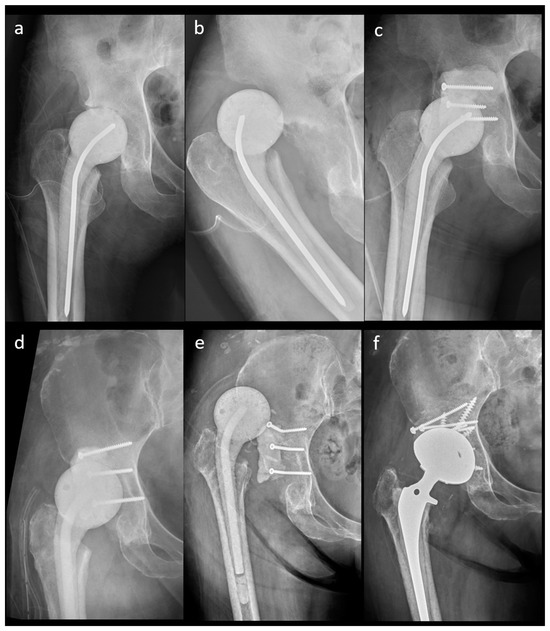

Figure 5.

A 41-year-old female patient with an n-MS spacer: (a) post-operative radiographs, (b) posterior dislocation 2 weeks after spacer insertion, and (c) open reduction combined with temporary cement tectoplasty. A 68-year-old male patient with an n-MS spacer: (d) open reduction combined with tectoplasty after posterior dislocation 4 weeks after spacer insertion, (e) recurrent dislocation after tectoplasty, and (f) acute reimplantation with bone grafting and cemented stem after the dislocation event and free of complications.